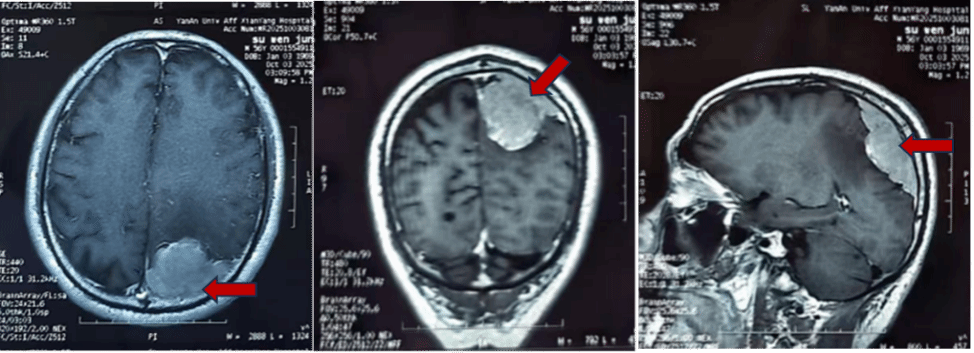

半年前,56岁的苏先生开始出现右手无力,每次发作约一天后自行缓解,无头痛头晕等不适,他便未予重视。直到数月后,同样的症状再次袭来,且右手活动明显受限,他这才意识到不对劲,立即赶往当地医院就诊。头颅磁共振检查的结果令人心惊——他的左侧头颅顶部有一个约6*8cm的巨大占位,近乎成年人的拳头大小,医生初步判断为脑膜瘤。

辗转多家医院后,苏先生带着最后的希望,来到我院神经外科。入院后进一步检查发现,这颗“拳头”已经压迫并侵袭了脑部重要的静脉血管——上矢状窦。神经外科千超主任医师、张毓主任医师及李海马博士团队迅速评估后指出,若不及时手术,肿瘤及周围水肿面积会继续扩大,最终将导致右侧肢体永久性偏瘫。开颅肿瘤切除术,是解除压迫、根治疾病的唯一选择!